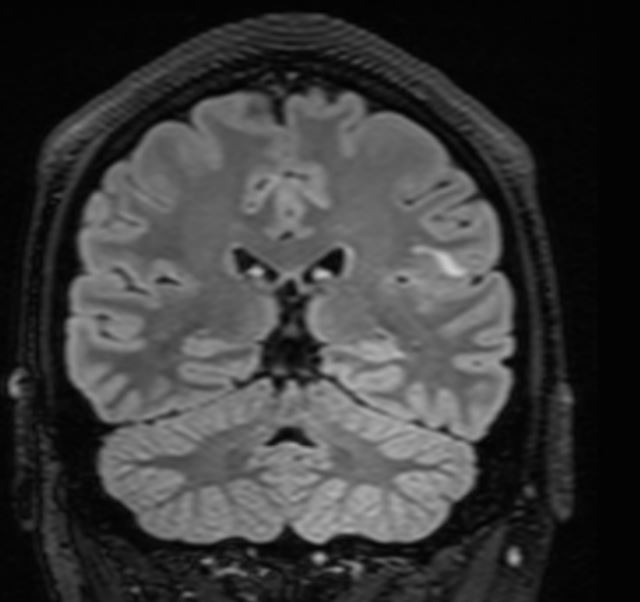

The MRI demonstrates a juxta-cortical, linear lesion in the white matter of the left post central gyrus extending medially to above the insular cortex. There is no mass effect and no enhancement. The nature of the lesion is unclear and does not relate to any of his symptomatology. His loss of consciousness almost certainly was related to a very large binge on alcohol, with very high blood alcohol levels. There is no history of any right facial or any other sensory symptomatology, nor of any episodic or persistent language dysfunction. There is no history of previous cranial trauma. His perinatal and developmental history is unremarkable.

In addition to the above lesion there are a few other punctate white matter lesions. It is presumed that these are old and have been discovered coincidentally as they do not relate to any past or recent symptomatology and are therefore "asymptomatic". I discussed the case with experienced neuroradiologist who reports that the lesions appear "innocuous".  The case also makes the point that diagnostic tests may result in a lot of harm; in this instance the patient was effectively "medically deported" within 24 hours of the scan having been done in a highly developed country. If the EEG is misinterpreted, the patient's problems will only be compounded. His EEG was normal for 72 hours; the rationale for performing it for this duration will be discussed at a later stage